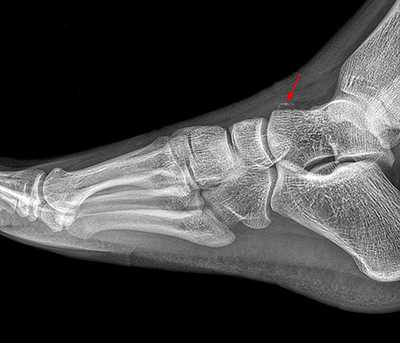

Рентгенологическое исследование

Для диагностики повреждения сустава Шопара делают рентген, КТ и МРТ. На передне-задней рентгенограмме определяют величину пяточно-кубовидного угла. Проводят одну касательную к наружному краю кубовидной кости и вторую касательную к наружному краю пяточной кости. В норме угол между касательными колеблется в пределах от 0 до 5°. Увеличение угла свидетельствует о нарушении стабильности пяточно-кубовидного сочленения. КТ во фронтальной и сагиттальной плоскостях позволяет выявить дефект суставных фасеток, смещение костей при вывихе и фрагментацию костей при переломе. КТ, по сравнению с рентгенографией, является более информативным методом диагностики. МРТ позволяет выявить дефекты отдельных связок.

Рис. 6. Отрывной перелом по тылу таранной кости на границе с суставом Шопара

Рис. 7. Перелом кубовидной кости по передней поверхности